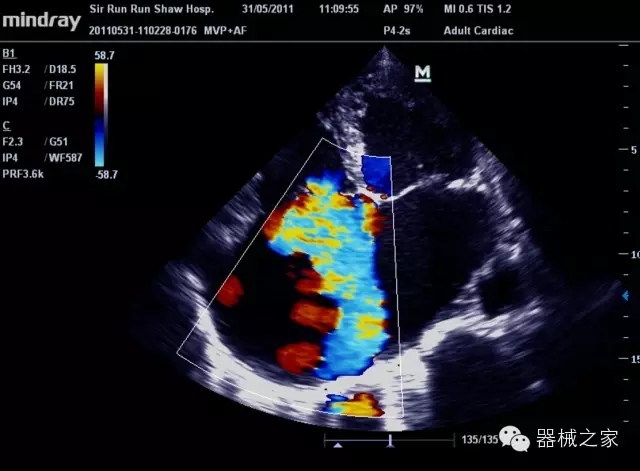

臨床圖片賞析

產(chǎn)品特點(diǎn)

8倍波束并行處理系統(tǒng)

·在便攜式緊湊平臺(tái)上采用更多倍波束并行接收信號(hào)處理模式,無論二維還是彩色血流圖像狀態(tài)下,擁有更靈敏的回波頻移捕獲能力,大大提高時(shí)間分辨率,尤其使得心血管表現(xiàn)更為突出;